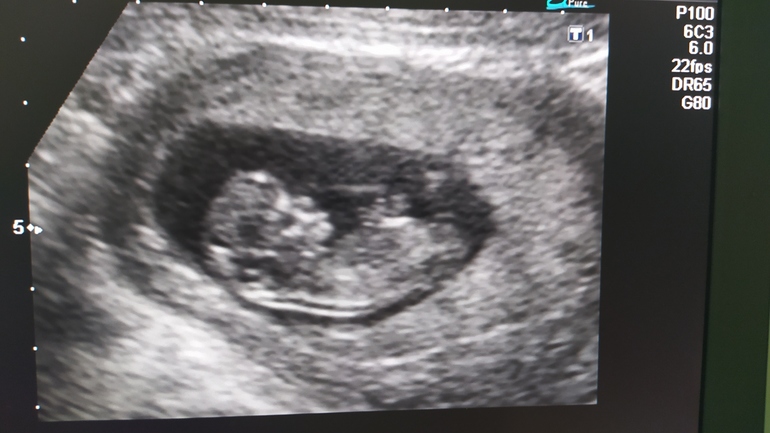

Кто умеет определять пол ребенка по фото?

Интуитивно мальчик, но знаете , как говорят врачи - точно только после родов)))

Ну по фото на мальчика похоже) а так полового бугорка не видно

Мне врач сказал что мальчики почти всегда растопыривают ноги " мужик на диване" поза у них эта с утроба) Так вот по позе " типичный мужик на диване" мальчик.

Сейчас вижу девочку

По форме головы не понимаю, но чисто интуитивно - мальчик.